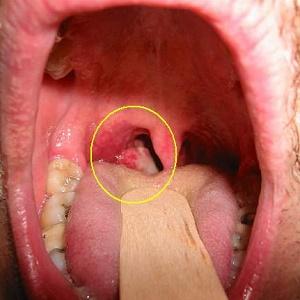

Дополнительными признаками могут быть заметные изменения в области носоглотки, сопровождающиеся воспалением и увеличением шейных лимфатических узлов, что можно увидеть на изображениях. Также стоит обратить внимание на ослабление лицевых мышц и онемение кожи на лице.